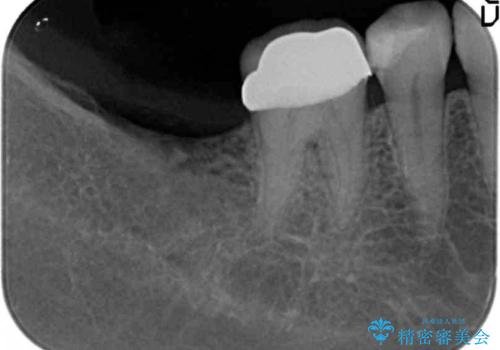

伸びてしまった奥歯、咬合平面を揃えたインプラント治療

- 右下の歯を虫歯で抜去し、インプラント治療を希望され来院されました。

インプラントを埋入するのに十分な骨は存在しますが、放置した間に上の歯が伸びてきてしまいクラウンのスペース不足な状態です。

通常このような場合、神経を除去し歯を短くしたのちインプラント治療を行いますが、今回はマイクロインプラントを用いて歯を歯ぐきの方向へ沈めたのち神経を温存する形でインプラント補綴を行いました。